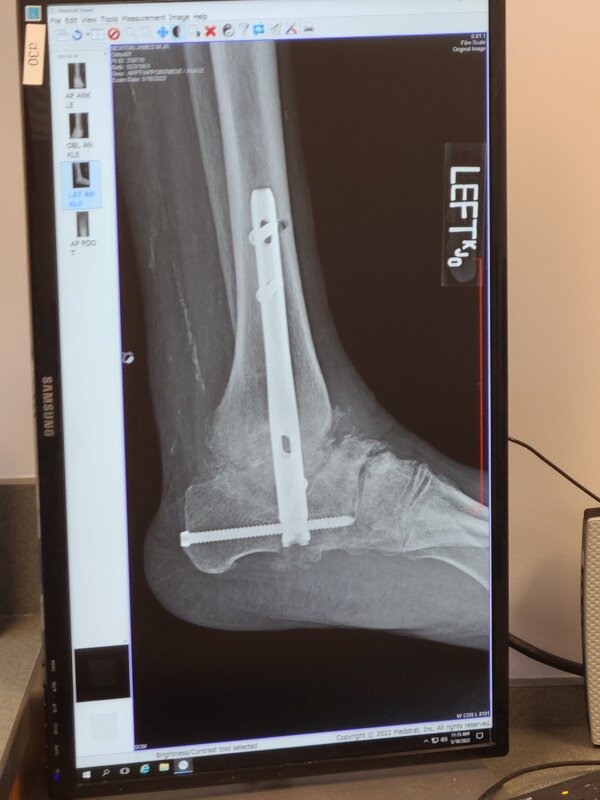

I can now get the foot wet, and I have been cleared for full weight bearing on my leg by the 10th, having gotten my cast removed, and been fitted for my new "walking boot" today.

View attachment 723378View attachment 723380View attachment 723379